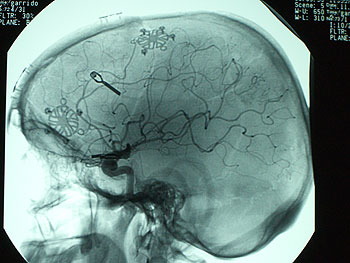

Two types of arteriovenous malformations of the brain can be treated with gamma knife radiosurgery: true arteriovenous malformations and cavernous angiomas. The former is characterized by a high-flow arteriovenous fistula with a large conglomeration of abnormal blood vessels that connect directly from the arterial to the venous side of the circulation. These patients are at risk for intracranial hemorrhage. Patients with cavernous angiomas have a lower bleeding risk, but if they have a documented history of cerebral hemorrhage, treatment is warranted.

Gamma knife radiosurgery tends to obliterate true arteriovenous malformations within 2 to 3 years of treatment. We treated 22 patients with true arteriovenous malformations, and 14 patients with cavernous angiomas. The results have been excellent, and no patient has suffered a recurrent hemorrhage (Figures 4 and 5).

Figure 4. Left parietal lobe arteriovenous malformation prior to gamma knife radiosurgery.

Figure 5. Four years following gamma knife radiosurgery, the arteriovenous malformation had completely resolved.